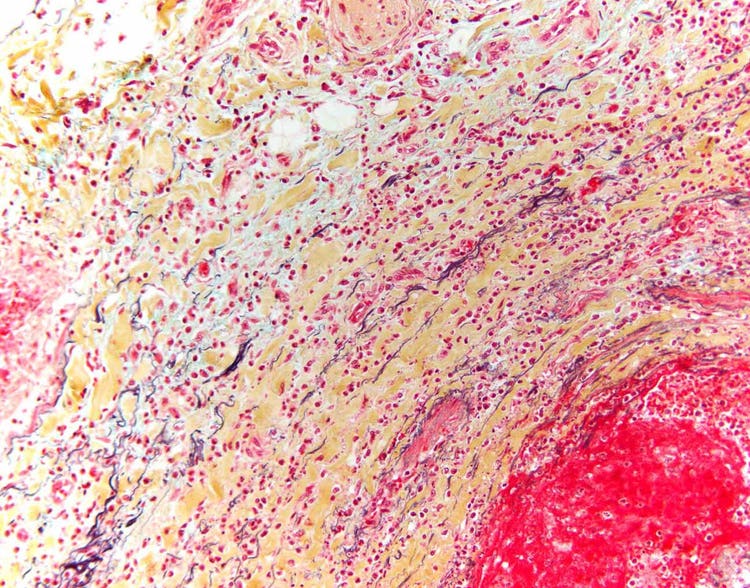

Tejido humano con amiloidosis visto bajo el microscopio

Sección de tejido humano tratada con una tinción especial de rojo Congo y observada bajo luz polarizada, lo que revela la presencia de la proteína amiloidea. La amiloidosis, una enfermedad que provoca el depósito inadecuado de proteínas en los tejidos humanos, presenta un brillo de color verde manzana bajo luz polarizada. Captura llevada a cabo con un microscopio Olympus BX43 dotado de una cámara DP26. Imagen por cortesía de Marianne Hamel.